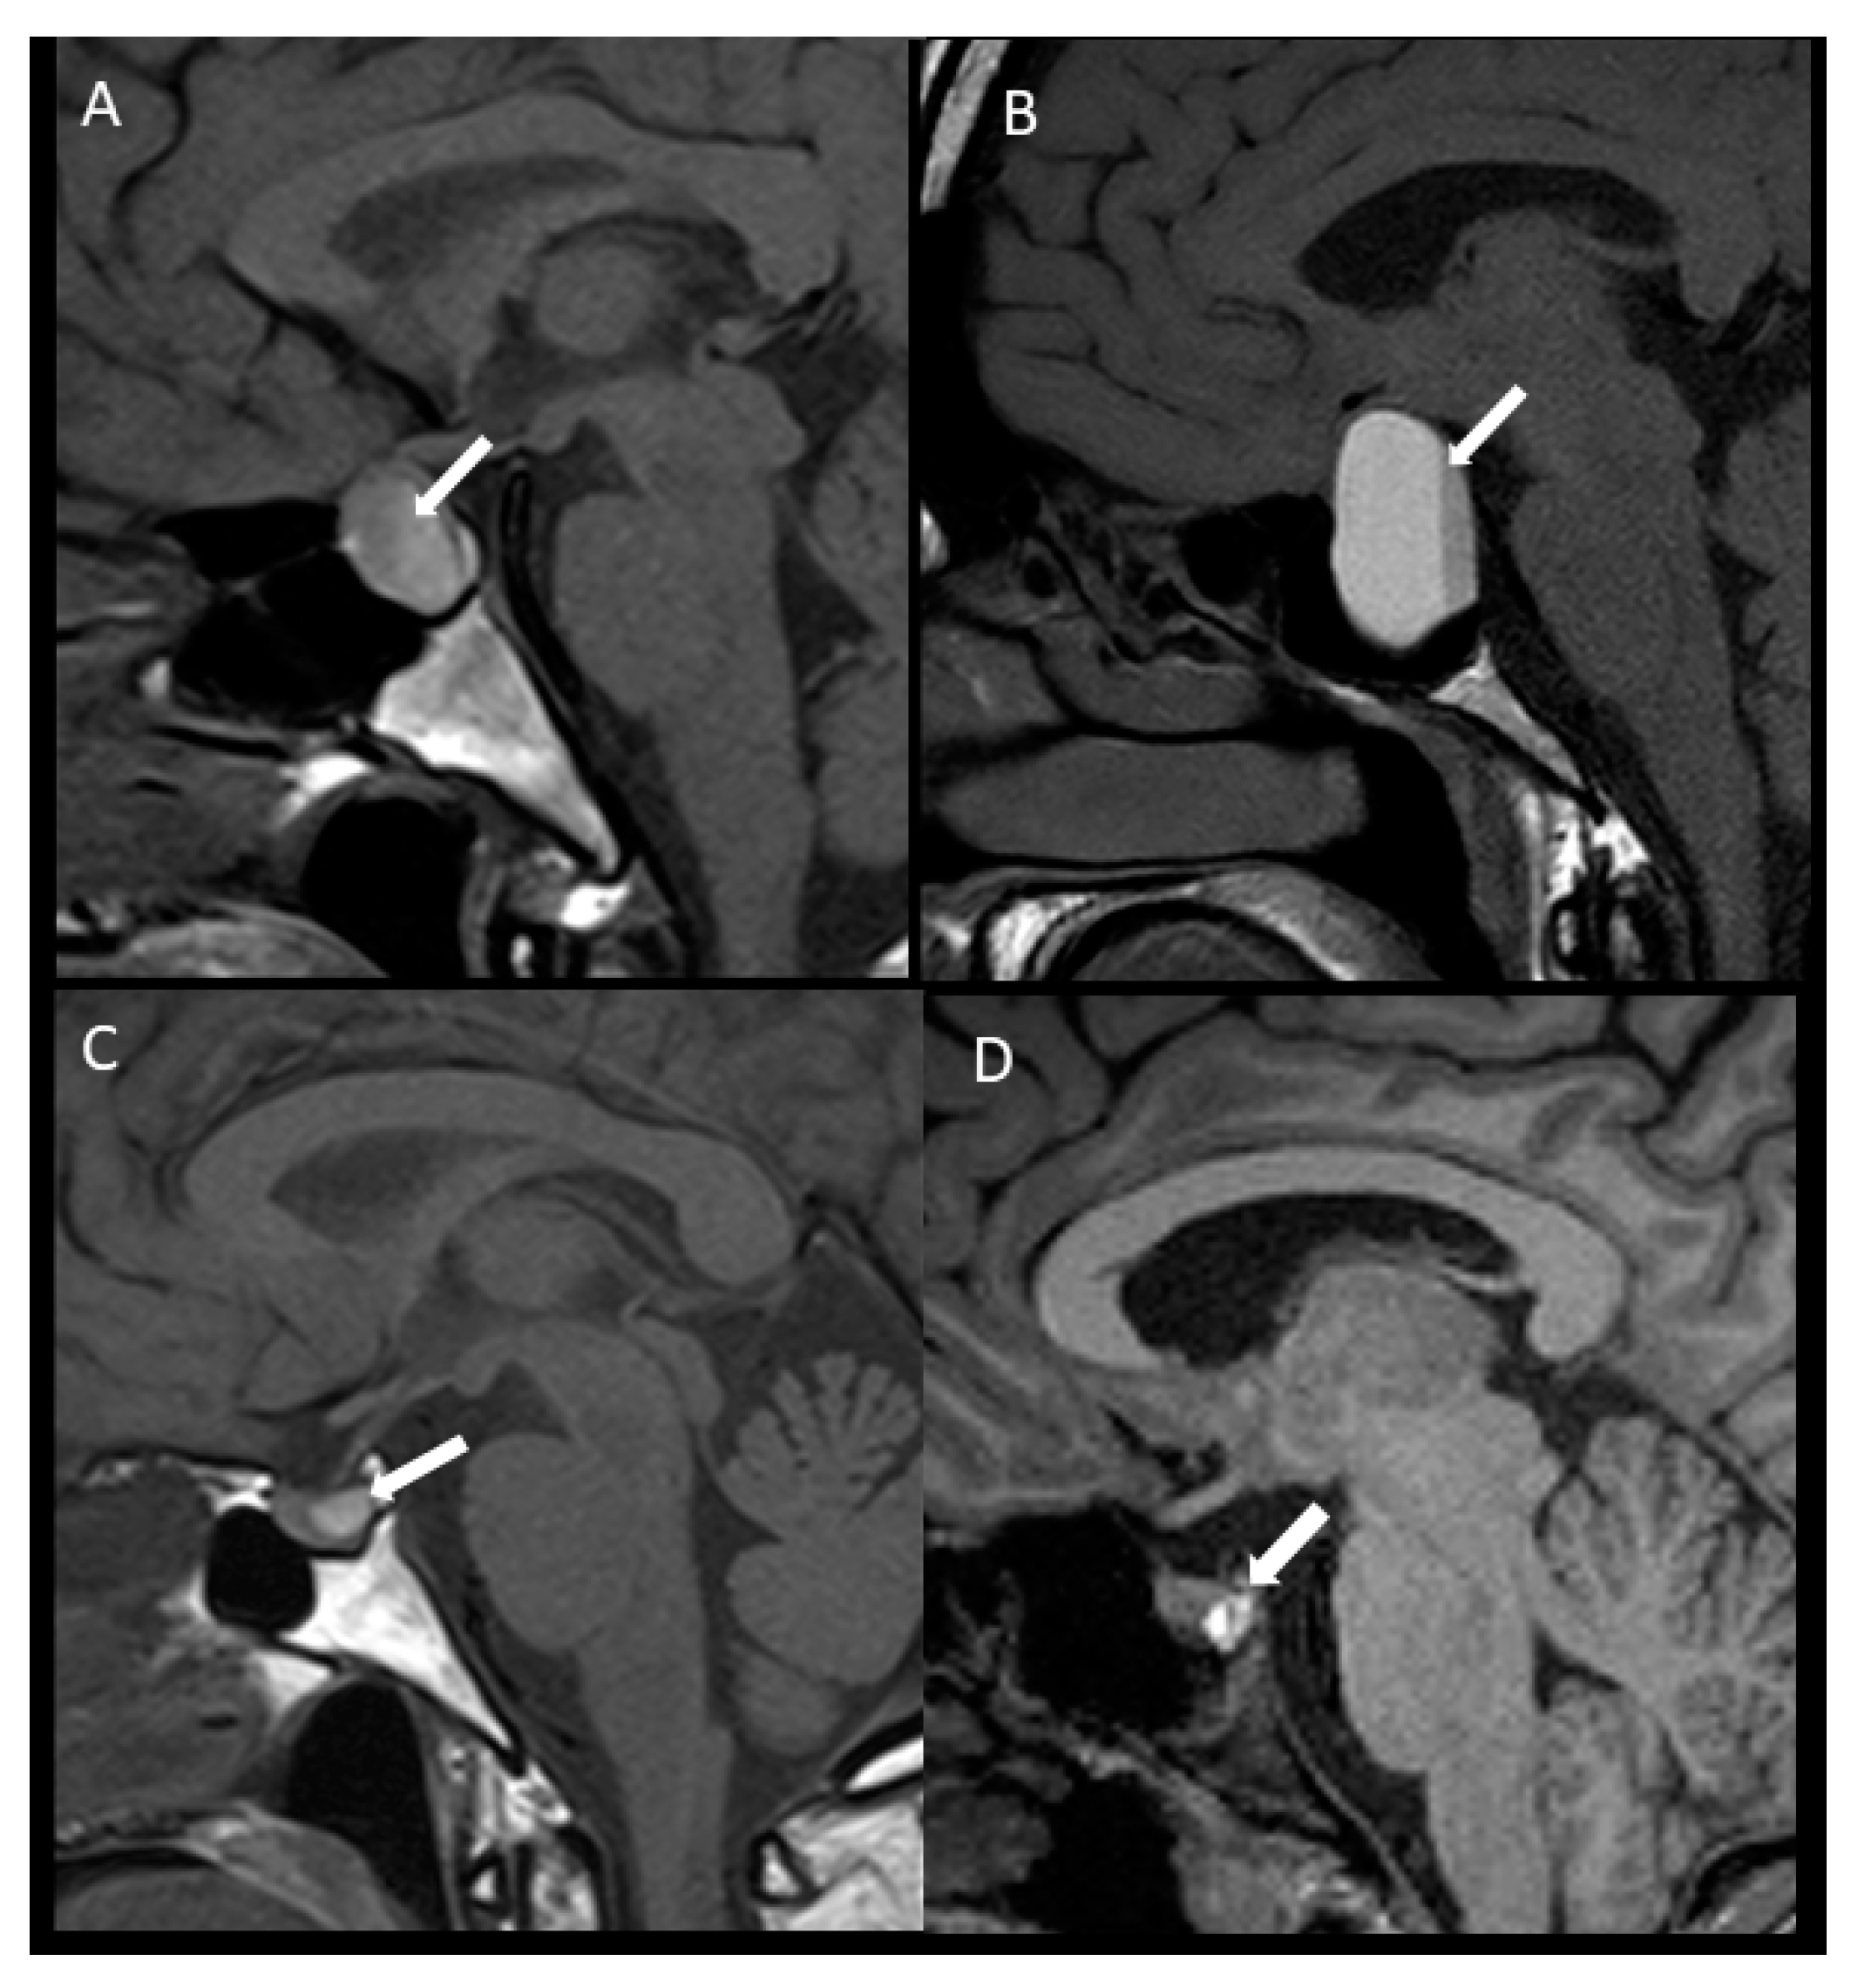

| T1 hyperintense (n, %) | 26 (70.3) | 8 (100) | 18 (62.1) | 0.04 |

| Radiological Hemorrhage | 6 (16.2) | 3 (37.5) | 3 (10.3) | 0.14 |

| Radiological Infarction | 3 (8.1) | 0 | 3(10.3) | 0.14 |

| Mixed radiological Hemorrhage/Infarction | 28 (75.7) | 5 (62.5) | 23(79.3) | 0.14 |